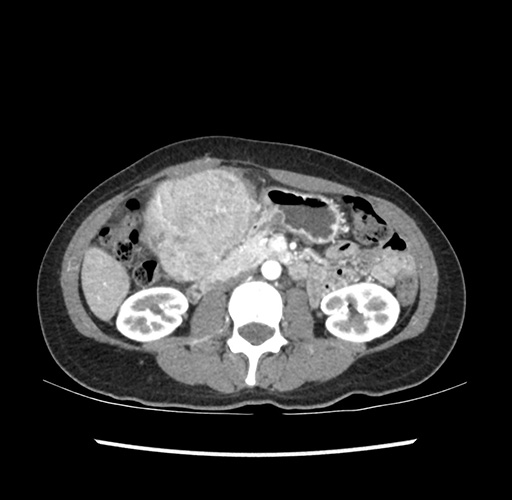

Imaging Analysis

Look through the patient's CT scan to identify any areas of concern for the necessary procedure.

Based on your CT findings, which issue(s) would give reason for "planned slowing down moment(s)" in this case?